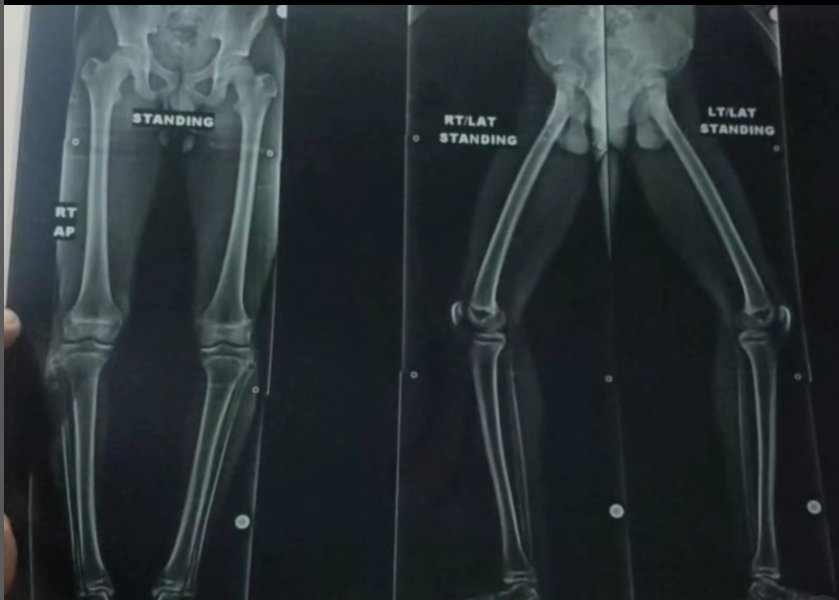

Case Study 7 - X-Ray Assessment

Comprehensive X-Ray Assessment

Standing AP and lateral X-ray views for lower limb alignment assessment, crucial for diagnosing musculoskeletal conditions and treatment planning.